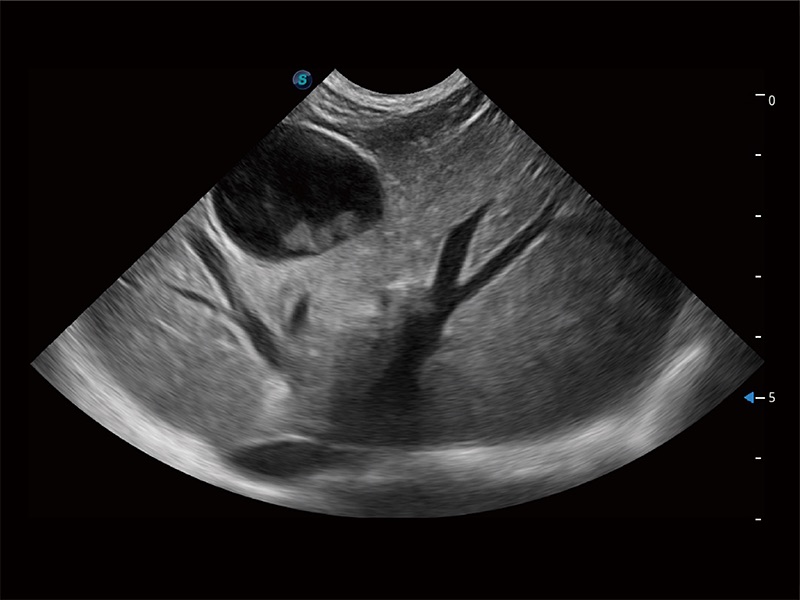

ProPet 80 配备了丰富的心脏探头群、先进的成像技术和专业的心脏测量工具,可帮助动物医生为不同体型和生理结构的动物提供心脏和心肌功能的全面评估。

实时用颜色表示心肌组织运动,观察和定量组织的运动情況,对快速检测与评估心肌的灌注和活性、电传导及心肌收缩和舒张功能等均能提供重要的诊断信息。

通过360度任意调节3条M型取样线,在同一心动周期上观察心脏不同位置的运动曲线,得到准确的心功能测量数据,有效评估心肌运动及左心室功能。